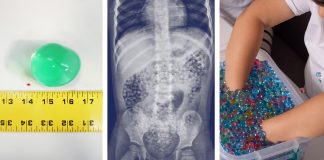

‘Water Beads Are Not Toys:’ Pallone, Child-Safety Groups Call for National...

NEPTUNE CITY – It might be time to cross water beads off the holiday toy list.